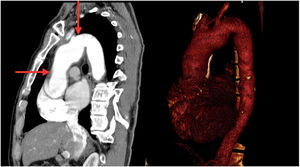

CasoPaciente masculino de 56 años, con antecedente de hipertensión arterial, quien consultó a una institución de tercer nivel de Medellín por cuadro clínico de tres días de evolución consistente en parestesias y hemiparesia del hemicuerpo derecho, asociado a disartria y asimetría facial; negaba síntomas cardiovasculares. Una tomografía de cráneo simple realizada a su ingreso, mostró área hipodensa en región gangliobasal izquierda compatible con lesión isquémica. Se amplió estudio para determinar etiología del infarto cerebral, encontrando VDRL reactivo en 128 dils y FTA-ABS positivo. En ecocardiografía transesofágica se evidenció válvula aórtica trivalva con insuficiencia severa, secundaria a perforación de la valva coronariana derecha, dilatación de la raíz aórtica con engrosamiento intimal difuso y calcificaciones en la unión sinotubular y en la curvatura menor del cayado aórtico (fig. 1). Se practicó arteriografía coronaria en la que se encontró dilatación de la aorta torácica ascendente con formación de aneurisma en el tercio medio del cayado aórtico y oclusión en el ostium de la arteria coronaria derecha. Una angiotomografía de tórax confirmó dilatación aneurismática de la aorta ascendente de 45mm de diámetro (fig. 2). En vista de los hallazgos imagenológicos descritos en presencia de serología reactiva para sífilis, se consideró probable aortitis sifilítica. Se hizo recambio valvular aórtico exitoso, por bioprótesis y bypass aorto-coronario a la descendente posterior (fig. 3). El aneurisma de la aorta ascendente no cumplía criterios de diámetro que obligaran a su corrección. El estudio histológico del material quirúrgico arrojó cambios degenerativos; en la aorta se observó vasa vasorum con infiltrado inflamatorio de células mononucleadas, mientras que la tinción de Warthin-Starry fue negativa.